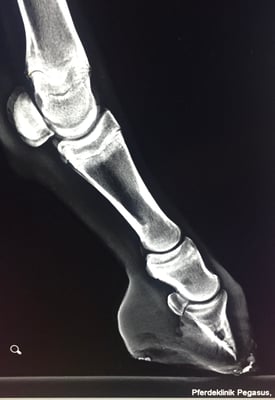

Die Zusammenarbeit von Veterinärtechniker und Tierarzt ist unerlässlich. Röntgenbilder sind absolut notwendig, um die Position des Hufbeines in der Hornkapsel zu erkennen und Sohlen- u. Wandstärke zu beurteilen. Dies ist

maßgebend für die Rehehuf- Korrektur und die Anfertigung des Hufschutzes, einem der Situation angepasster Klebebeschlag. Jeder Rehehuf ist anders, daher gibt es keinen Standardbeschlag. Der Klebebeschlag

• Hufrehe, Haflinger in Oberösterreich

Der Rehe-Huf wurde nach Sichtung der Röntgen Bilder und Rücksprache mit dem Tierarzt korrigiert. Ein reheadaptierter Duplo Beschlag mit Strahlunterstützung wurde angefertigt.